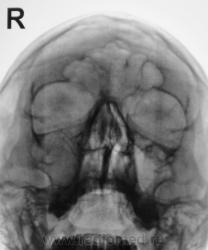

1 срез.

я не вижу четко стенок в.челюстной пазухи справа - атрфия от давления? может мукоцеле?

ассиметрия есть..